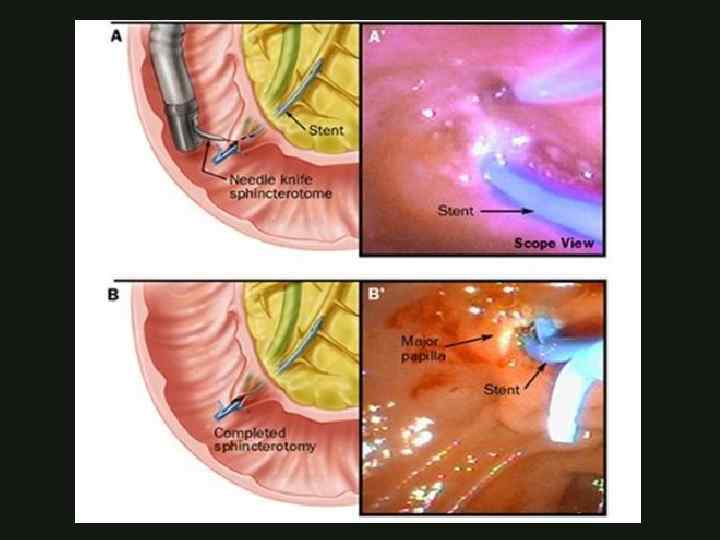

ЭНДОСКОПИЧЕСКОЕ ЛЕЧЕНИЕ ОСТРОГО ОТЕЧНОГО ПАНКРЕАТИТА Эндоскопическая папилосфинктеротомия Эндоскопическое стентирование ЭРХПГ КАФЕДРА ХИРУРГИИ МОСКОВСКОГО ФАКУЛЬТЕТА

ЭНДОСКОПИЧЕСКОЕ ЛЕЧЕНИЕ ОСТРОГО ОТЕЧНОГО ПАНКРЕАТИТА Эндоскопическая папилосфинктеротомия Эндоскопическое стентирование ЭРХПГ КАФЕДРА ХИРУРГИИ МОСКОВСКОГО ФАКУЛЬТЕТА